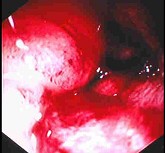

男,18岁,患者皮肤挫伤,用林可霉素预防感染,次日大便次数增多、出现粘液便,结合图像应考虑为( )

A:结肠淋巴瘤

B:假膜性肠炎

C:结肠间质瘤

D:结肠结核

E:结肠癌